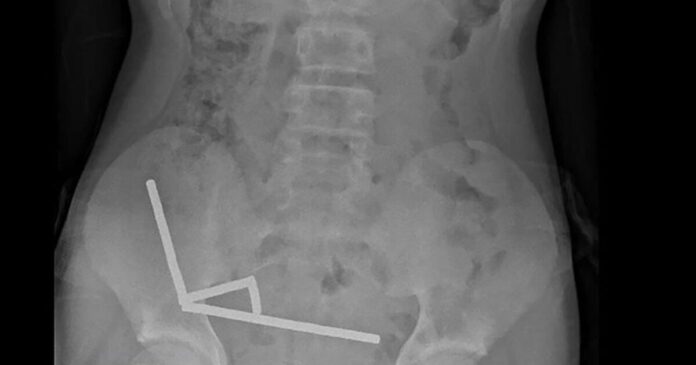

Η ακτινογραφία έδειξε ότι οι μαγνήτες είχαν συγκεντρωθεί σε τέσσερις ευθείες γραμμές μέσα στα έντερα του παιδιού, όπως φάνηκε και στην ακτινογραφία.

«Φαινόταν ότι βρίσκονταν σε διαφορετικά σημεία του εντέρου, τα οποία είχαν κολλήσει μεταξύ τους λόγω των μαγνητικών δυνάμεων», αναφέρει η έκθεση.